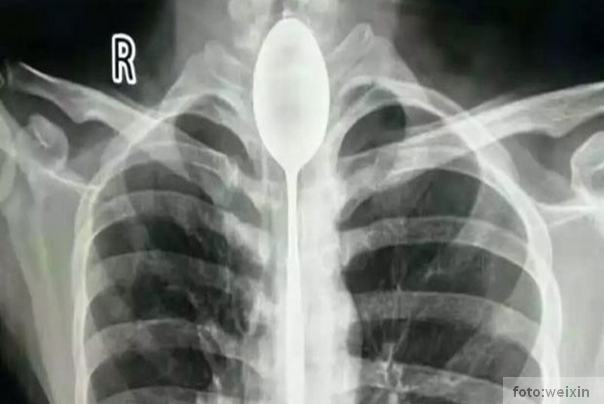

Kinez godinu dana živeo s kašikom u grlu!

Lekare u kini šokirao je slučaj pacijenta koji se požalio da jedva diše. Kako se kasnije ispostavilo na rentgenu su primetili kašiku dužine 20 centimetara na neobičnom mestu….

u grlu muškarca, a što je još čudnije, mesecima mu nije mnogo smetala.

Mladić dvadesetih godina hteo je da impresionira prijatelje gutanjem pribora za jelo, i sve je bilo “u redu” dok ga neko nedavno nije udario u grudi.

Lekarima je trebalo dva sata da uklone strani objekat iz jednjaka čoveka koji se previjao u bolovima, ali je na kraju sve prošlo kako treba.

Jedan od lekara kaže da je bio veoma iznenađen i da nikada nije video nešto ovakvo. Takođe navodi da je mladić imao mnogo sreće jer je gutanje ovako velikih predmeta opasno po život.